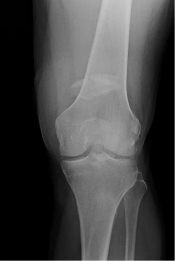

What’s the Diagnosis? Gepost op 5 april 20185 april 2018 door netwerkvsseh What’s the Diagnosis? @emdaily.cooperhealth.org Dit delen: Delen op X (Opent in een nieuw venster) X Share op Facebook (Opent in een nieuw venster) Facebook Delen op LinkedIn (Opent in een nieuw venster) LinkedIn E-mail een link naar een vriend (Opent in een nieuw venster) E-mail Afdrukken (Opent in een nieuw venster) Print Vind-ik-leuk Aan het laden... Gerelateerd